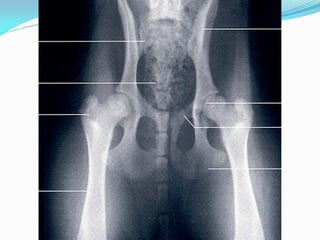

ARTICULAÇÃO ESFERÓIDEA -

EX: Articulação do quadril

(coxofemoral)

ARTICULAÇÃO ESFERÓIDEA - SEGMENTOSMAIORES QUE MEIA ESFERA, DE UM LADO CHEIO E DO OUTRO ESCAVADO. EX: Articulação do quadril (coxofemoral)